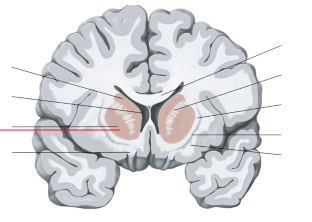

nucleus caudatus

putamen

globus pallidus

hippocampus

amygdala

fornix

laterale ventrikels (I en II)